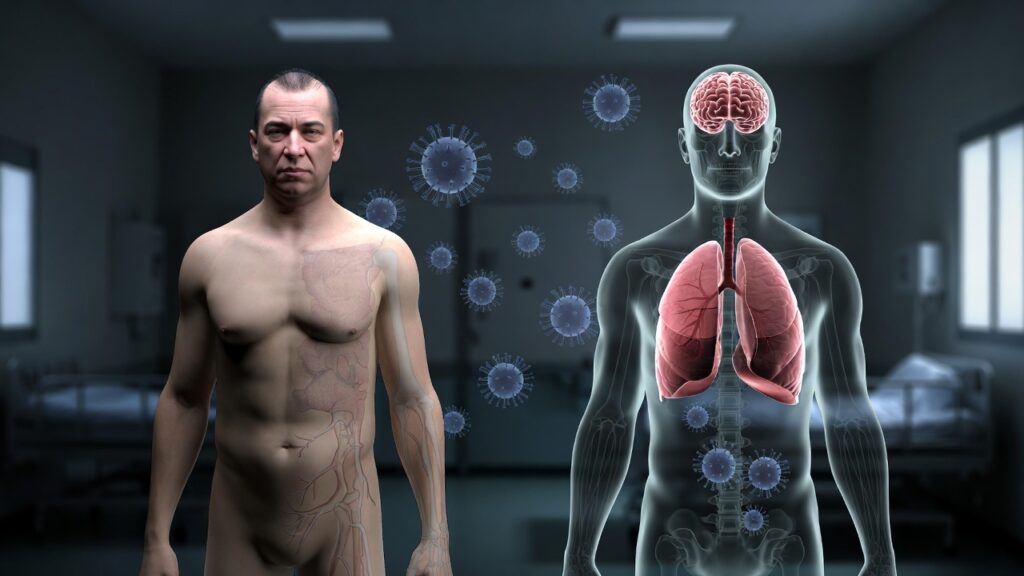

Nipah virus originates in animals and can be passed to humans through direct or indirect contact. It is classified under the Paramyxoviridae family and belongs to the Henipavirus genus, which also includes the equally lethal Hendra virus. Unlike many common viral infections, Nipah virus demonstrates a strong tendency to attack both the central nervous system and the respiratory system. This often leads to acute brain inflammation (encephalitis), serious breathing difficulties, and a high risk of mortality.

Modes of Transmission

- Animal-to-Human Transmission

o Contact with infected pigs or other animals

o Working with sick animals without protective gear

- Foodborne Transmission

o Consumption of bat-contaminated raw date palm sap

o Eating fruits partially eaten or contaminated by bats

- Human-to-Human Transmission

o Indirect contact with infected individuals’ bodily fluids o Droplets that are exhaled

o Close caregiving contact

o Poor infection control in healthcare settings